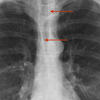

normal vessels

AP window